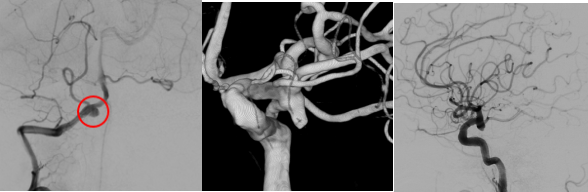

检查发现

“元凶”是大脑椎动脉上

一个形状不规则的“小气球”

——医学上称为“夹层动脉瘤”

它破裂了

脑血管造影(DSA):这是确诊并锁定动脉瘤的“金标准”。医生通过它能看到脑血管的清晰三维结构,明确“炸弹”的位置和形态,为手术铺路。